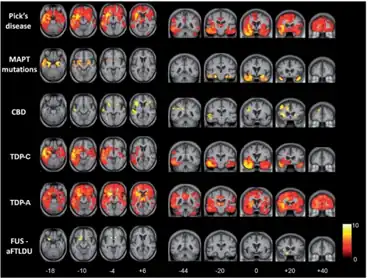

![]() | |